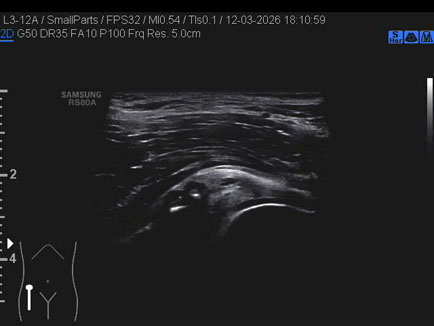

Data inserimento: 23/03/2026

Ecografia del: 12/03/2026

Strumento: Samsung

Sonda: Lineare

Commento all'esame: ganglio del cercine cotiloideo.

Conclusioni: ganglio del cercine cotiloideo (ganglion of the cotyloid labrum).

Realizzazione: Dr. F. Pietro Tarini - Gubbio (PG)

Presentazione: Dr. Massimo Dolciotti - Ancona